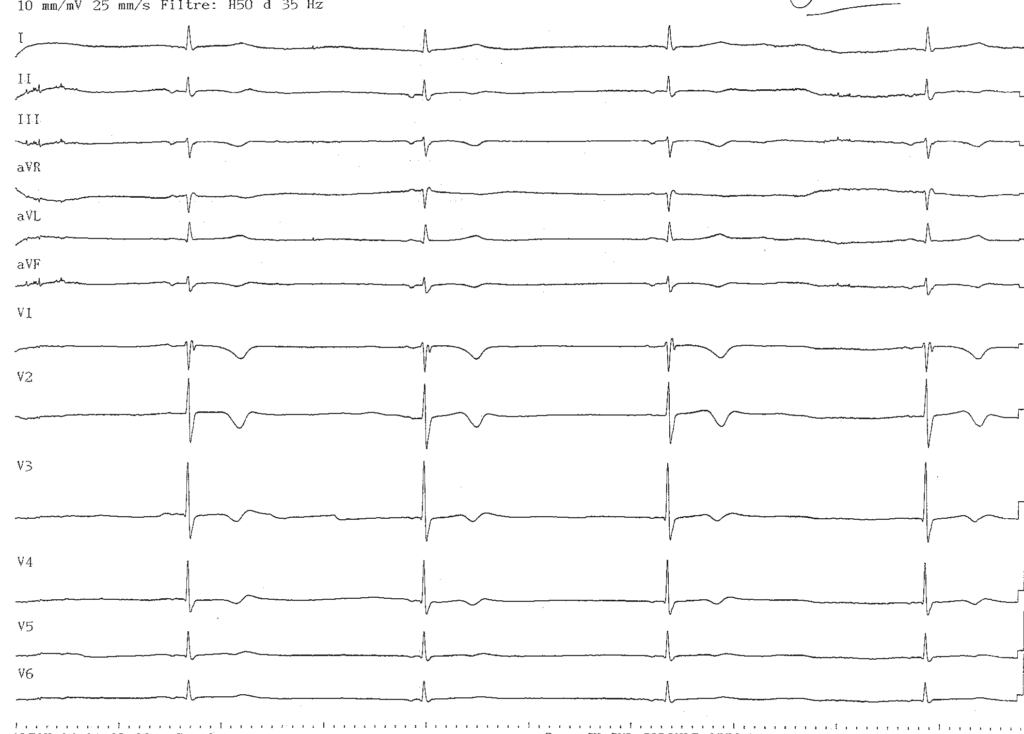

Description tracé

Bradycardie à 25 battements/minute; rythme d’échappement auriculaire provenant du sinus coronaire (activité atriale négative dans les dérivations inférieures, traduisant une activation provenant de la partie basse de l’oreillette), QRS fin (aspect morphologique proche de celui du QRS en tachycardie mais plus fin);